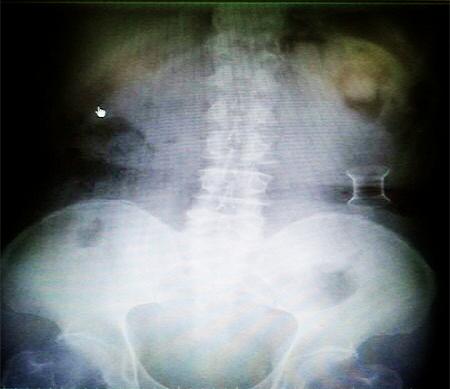

受試患者在結(jié)腸端端吻合術(shù)中,使用我司新研制產(chǎn)品達(dá)到了理想的預(yù)期效果。患者術(shù)后7天、14天X光片顯影,可降解腸道支架均能按研制設(shè)計(jì)的預(yù)期時(shí)間節(jié)點(diǎn)保持應(yīng)有強(qiáng)度,術(shù)后21天X光片顯示可降解腸道支架已完全破碎,并排出體外。在整個(gè)試驗(yàn)過(guò)程中,病患無(wú)任何不良反映,耐受良好。